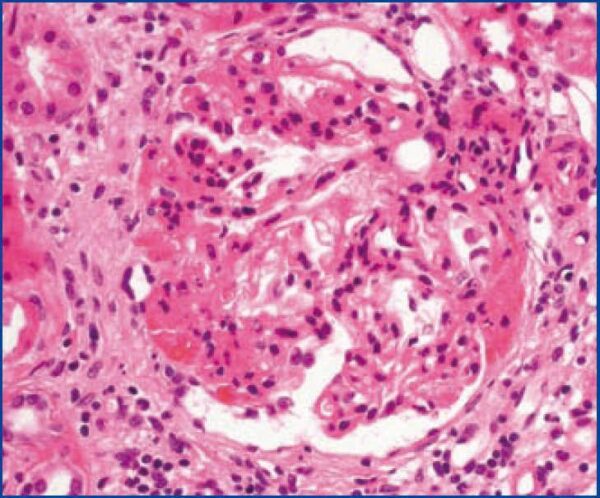

La glomeruloesclerosis segmentaria focal es un patrón de lesión renal que se presenta con relativa frecuencia y que resulta del daño a los podocitos, que son células especializadas que desempeñan un papel crucial en la función del glomérulo, la unidad básica de filtración del riñón. Este trastorno puede ser primario, es decir, limitado al riñón, o puede ser secundario a otra enfermedad subyacente.